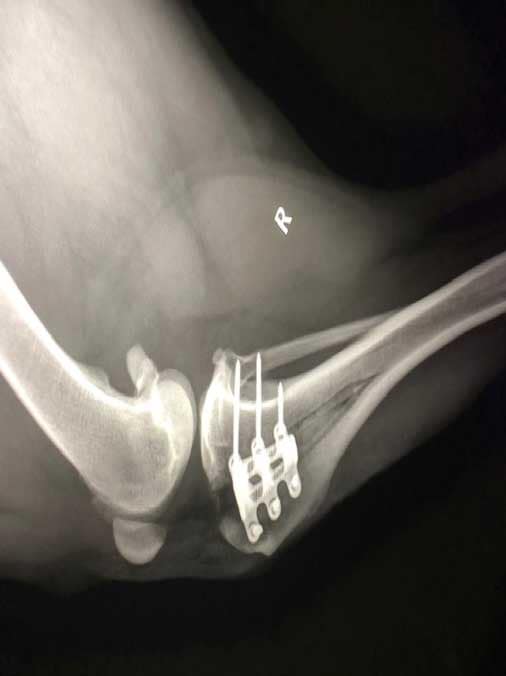

Hieronder links een foto van een gezonde knie en rechts een knie met gescheurde voorste kruisband. Hierbij valt op dat het onderbeen naar voren is geschoven bij de zieke knie.

TTA oftewel Tibial Tuberosity Advancement. De voorkant van het scheenbeen of tibia wordt hierbij ingezaagd en naar voren gebracht. Daardoor gaat ook de aanhechting van de kniepees naar voren.  Om deze verplaatsing te behouden wordt een TTA Rapid kooi geplaatst. Hierdoor veranderen de krachten die werken op het kniegewricht. Het onderbeen zal niet meer naar voren willen gaan, zodat de functie van een kruisband niet meer nodig is. Het goed bezenuwde en pijnlijke gewrichtskapsel staat niet meer op spanning. De knie komt als het ware in rust als de hond er op staat. Met als gevolg dat de knie rust krijgt om te herstellen. Ook komen er geen grote krachten meer op de meniscus in de knie. Eigenlijk maakt de chirurg van de hondenknie een mensenknie. Hiervoor moet er wel in het bot gezaagd en een implantaat met schroeven geplaatst worden. Dit maakt dat deze operatie duurder is dan een Flo techniek. Maar toch is de TTA Rapid goedkoper dan een oudere TTA of TPLO techniek. Hieronder een foto van een TTA Rapid kooi geplaatst in een nepknie.

• Operatie: controle meniscus, kapotte kruisband verwijderen, TTA Rapid kooi plaatsen, alle hechtingen plaatsen, laatste hechting van de huid ligt onder het vel.